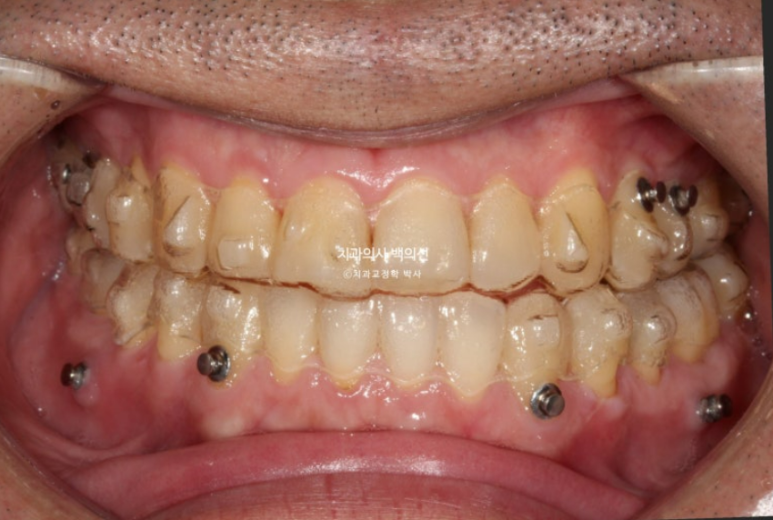

23년 12월 주걱턱 치료를 위해 오신 40대 환자분입니다.

골격적 주걱턱 뿐만 아니라 아래턱이 왼쪽으로 틀어진 비대칭도 보입니다.

23.12

앞니가 완전히 거꾸로 물립니다.

치열은 가지런한 편이나 앞니 반대교합으로 오랫동안 지내오면서 아래앞니에 부딫쳐 위 앞니 마모도가 심합니다.